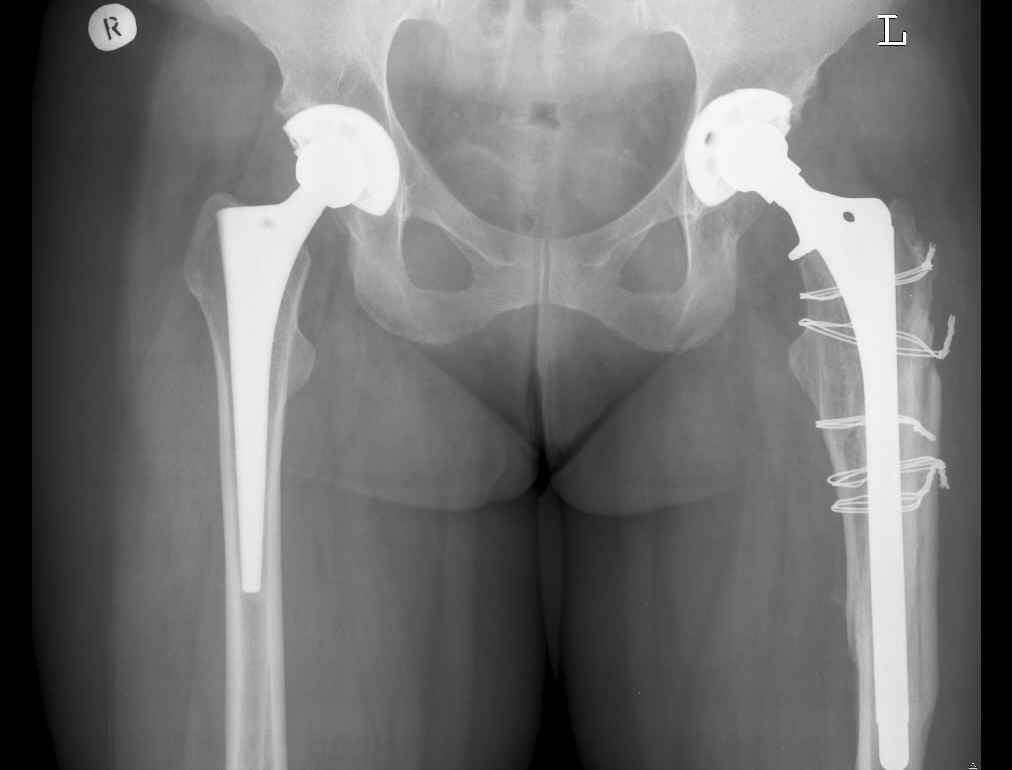

По Ванкуверовской классификации это 2А тип перипротезного перелома на фоне нестабильности ножки эндопротеза и остеолиза проксимального отдела бедра. Решение - удаление предыдущей ножки, имплантация ножки дистальной фиксации. Канал виден на ограниченном участке, исходя из увиденного, я бы предпочел цилиндрическую ножку 200 мм полнопокрытую. Фрагменты собрал бы вокруг ножки серкляжами. Если будут мелкие фрагменты, то есть смысл взять кортикальные аллографты и поджать фрагменты по типу вязанки хвороста. Отношение к чипсам двоякое - на любителя, главное - надежная дистальная фиксация ножки, обеспечивающая первичную стабильность. Что-то похожее мы оперировали несколько лет назад, качество первичных Р-грамм оставляет желать лучшего, но суть понятна. Результаты через 3 года.